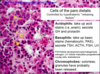

pancreas

How to differentiate zones of the cortex of the adrenal gland?

The zona fasiculata is much more pale staining and you see empty space here. The zona fasciculata cells have lipid components and this is extracted during staining. This is why it looks white. But these cells are also much more puffy looking compared to the cells around them. And finally over here is the zona reticularis.

In the zona fasciculata the cells are in straight cords, in the reticularis you can see much more branching rather than straight lines.